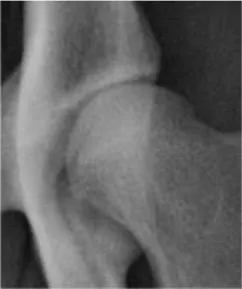

Initially, a best fit circle outlining the femoral head was drawn to define its center and calculate its area. Norberg and inclination angles were measured according to the previously published veterinary literature (13, 14, 2729). Center-edge (CE) and acetabular index angles were modified from the previously established human procedures (9, 10, 15, 16, 30). The CE angle was measured between two straight lines originating from the center of the femoral head, a line tangential to the lateral acetabular rim and a second line parallel to the longitudinal axis of the body of the corresponding ilium (iliac axis) (14) (Figure 1A). The acetabular index/slope angle formed between a line connecting the lateral and medial extents of the sclerotic cranial acetabular edge (acetabular sourcil slope) and a horizontal line perpendicular to the corresponding iliac axis (Figure 1B).

Figure 1. Ventrodorsal pelvic radiograph of a mildly dysplastic coxofemoral joint illustrating measurements of Center-edge angle (Φ) (A) and acetabular index/slope angle (α) (B). a, long axis of the iliac body; b, a line originating from the femoral head center and tangential to lateral acetabular rim; c, a line tangential to lateral and medial extents of the cranial acetabular rim (acetabular sourcil); d, a horizontal line perpendicular to the iliac axis (a).